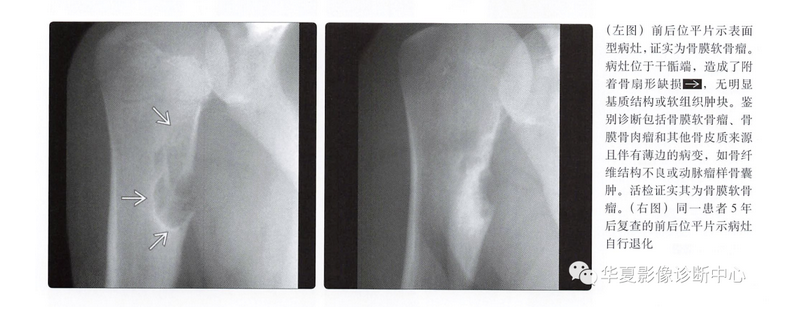

平片表现

- 骨皮质扇形凹陷

- 硬化边

- 致密性骨膜反应,尤其是在病灶近端、远端

- 病灶远端、近端骨皮质杯状改变

- 基质钙化(75%)

- 软组织肿块

骨膜软骨肉瘤

- 很少见的表面型软骨肉瘤

- 与骨膜软骨瘤发病部位相同

- 通常为低度恶性,因此可能不会出现明显侵袭性

- 几乎与骨膜软骨瘤影像表现相同

- 骨表面病灶

- 骨皮质呈扇形塌陷改变

- 基质钙化

自然病史及预后

- 缓慢进展的局限性病灶